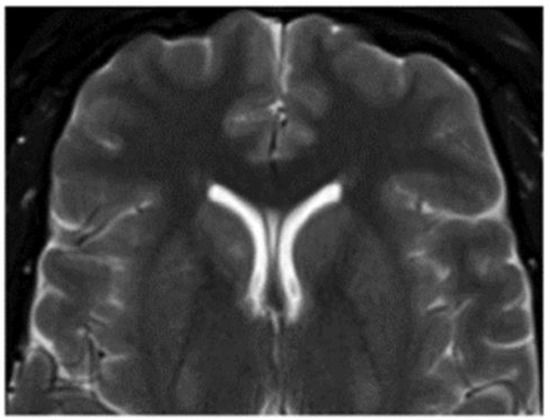

3.1. Venous Malformations

3.1.1. Cerebral Venous Malformations